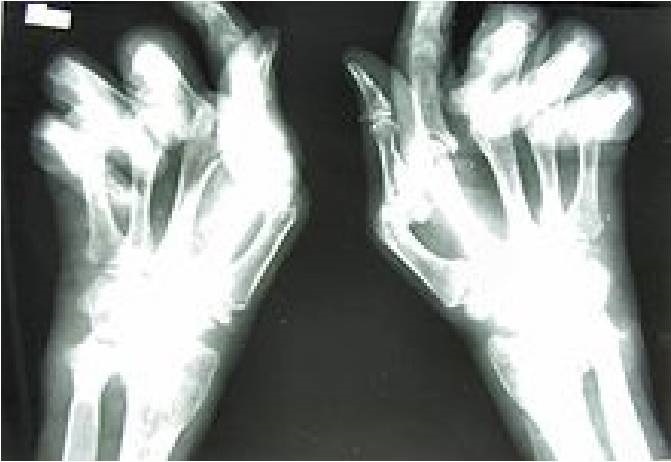

Teorie te wydają się potwierdzać wyniki, opublikowanego na łamach Journal of Bone and Mineral Research, badania obejmującego populację blisko 20 tys. chorych na reumatoidalne zapalenie stawów (RZS), których dane zgromadzone zostały w narodowej bazie danych (National Data Bank for Rheumatic Diseases), na przestrzeni lat 2003 – 2011. Ryzyko zawału mięśnia serca było istotnie mniejsze wśród chorych na RZS stosujących bisfosfoniany, w porównaniu do nie leczonych tymi lekami (0,72), po uwzględnieniu występujących czynników ryzyka sercowo-naczyniowego, aktywności choroby podstawewej oraz sprawności. W wyselekcjonowanej grupie pacjentów, którzy kiedykolwiek stosowali bisfosfoniany, cęstość zawału była mniejsza u chorych aktualnie przyjmujących bisfosfonian (0,56), w porównaniu do chorych nie leczonych. Wykazano ponadto, że najsilniejszy efekt protekcyjny miało stosowanie kombinacji trzech leków: bisfosfonian, witamina D, wapń.